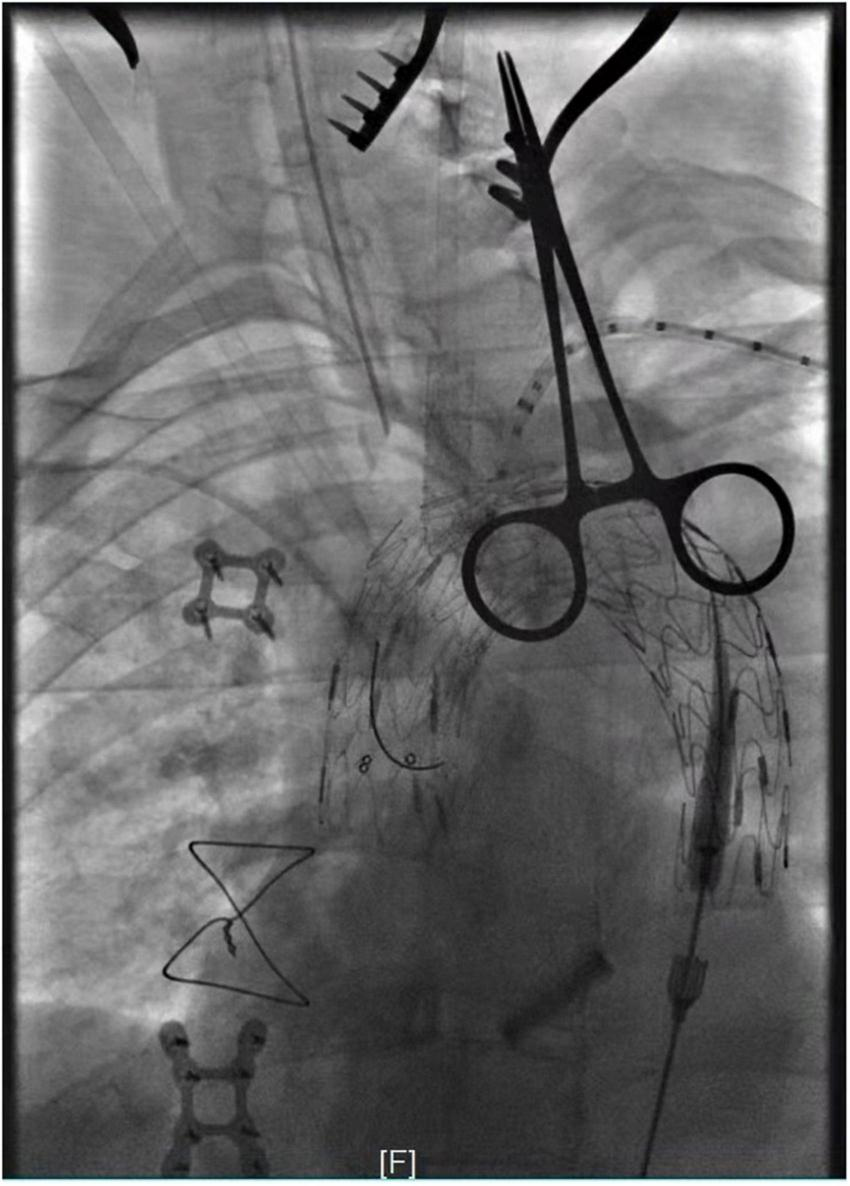

After rapid establishment of blood flow to the LCA, the IA was fenestrated in situ in the same way (Figure 3). After stenting of the IA, the temporary bypass was removed. Then we perform the left subclavian artery (LSA) in situ fenestration. We used the Fustar™ Steerable Introducer system (Lifetech Scientific, Shenzhen, China) for LSA in situ fenestration. It was a combination of long sheath and guiding catheter which the tip can be deflected. After introduced the Fustar sheath via the LSA, the tip was deflected in order to directly contact the fabric part of the main stent graft and in situ needle fenestration was applied. After the 0.018 guidewire penetrated into the stent graft, a balloon catheter was advanced inside the stent graft via the fabric covered of the stent graft and then dilated gradual by different sizes of balloons. Following dilatation of the balloon, a covered stent graft was implanted in the fenestration and DSA was applied to verify the patency of the endograft fenestration (Figure 4). During this period, if in situ fenestration is difficult to perform, the chimney technique is an option. The LSA would be occluded to prevent endoleak if not successful reconstruction the LSA and if the aneurysm cavity is large and endoleak is severe, the candy-plug technique or coil embolization can still be used for false lumen occlusion (14). After totally reconstruction of the supra-aortic branches, angiography was performed to confirm that there were no intra-operative problems, and the surgery was terminated (Figure 5).

FIGURE 3

Panel (A–C) showed in situ fenestration of the IA made by gradual balloon dilation (after the fabric part of the main stent-graft was punctured by using a hollow needle).